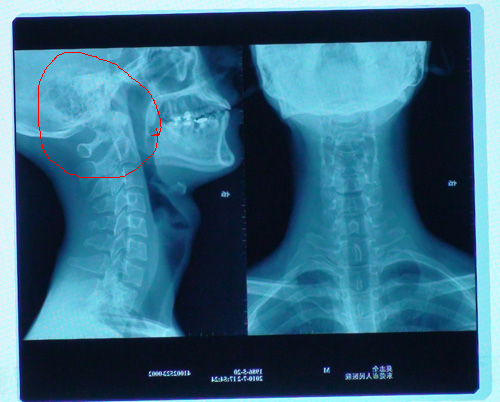

1、頸椎病:頸背疼痛、上肢無力、手指發麻、下肢乏力、行走困難、頭暈、惡心、嘔吐,甚至視物模糊、心動過速及吞咽困難。